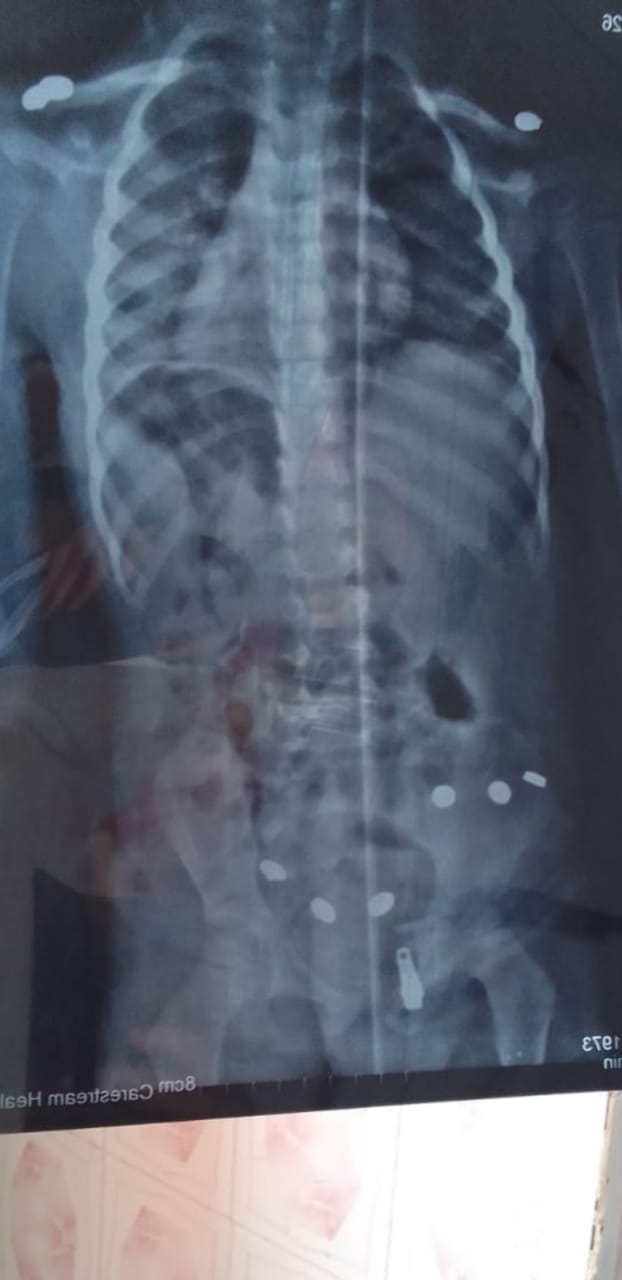

وفى ذات السياق قام فريق طبي بقسم الجراحة بنفس المستشفى بإجراء فك تداخل تليسكوبي بالأمعاء بدون تدخل جراحي واستكشاف البطن باستخدام جهاز الأشعة لطفل يبلغ من العمر عامين.